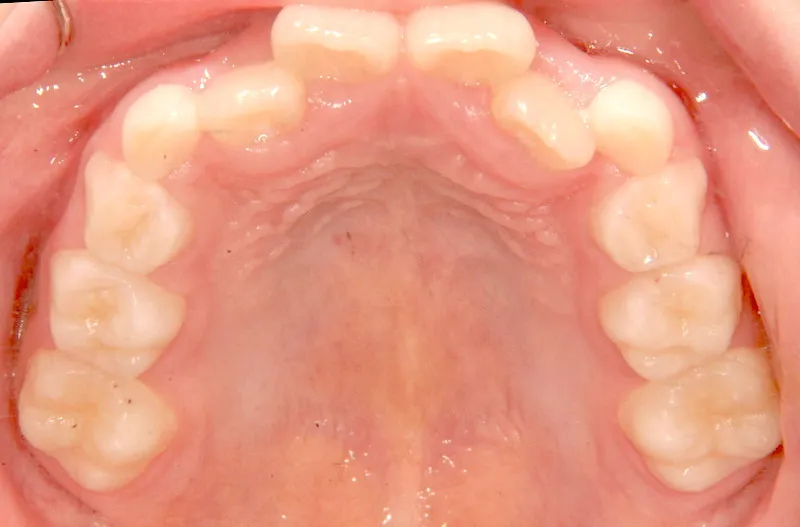

【子供の矯正(一期)】叢生・切端咬合・受け口・永久歯が生える隙間がない・非抜歯症例・8歳男子【K.Y様】

初診時年齢 小学校3年生 (男性) 主訴 前歯の噛み合わせが悪い

診断名 切端咬合 装置名

状態 永久歯が生える隙間がない(叢生)

受け口(下顎前突/反対咬合)

切端咬合

上の歯も下の歯も歯が生えるスペースが少ない為ガタガタしています。

前歯同士が上下で付き合わせる様に噛み(切端咬合)、

その横の歯は上の歯が下の歯の後ろにきて噛んでいる状態です(反対咬合)

まずは装置で歯のアーチを広げ、歯の生えるスペースを作り、中に入ってる上の前歯を外に押し出して正常な噛み合わせにします。

治療回数44回、5年5ヶ月の治療期間で矯正治療を終了しました。

主訴が改善され、ご満足頂きました。

初診

治療終了後